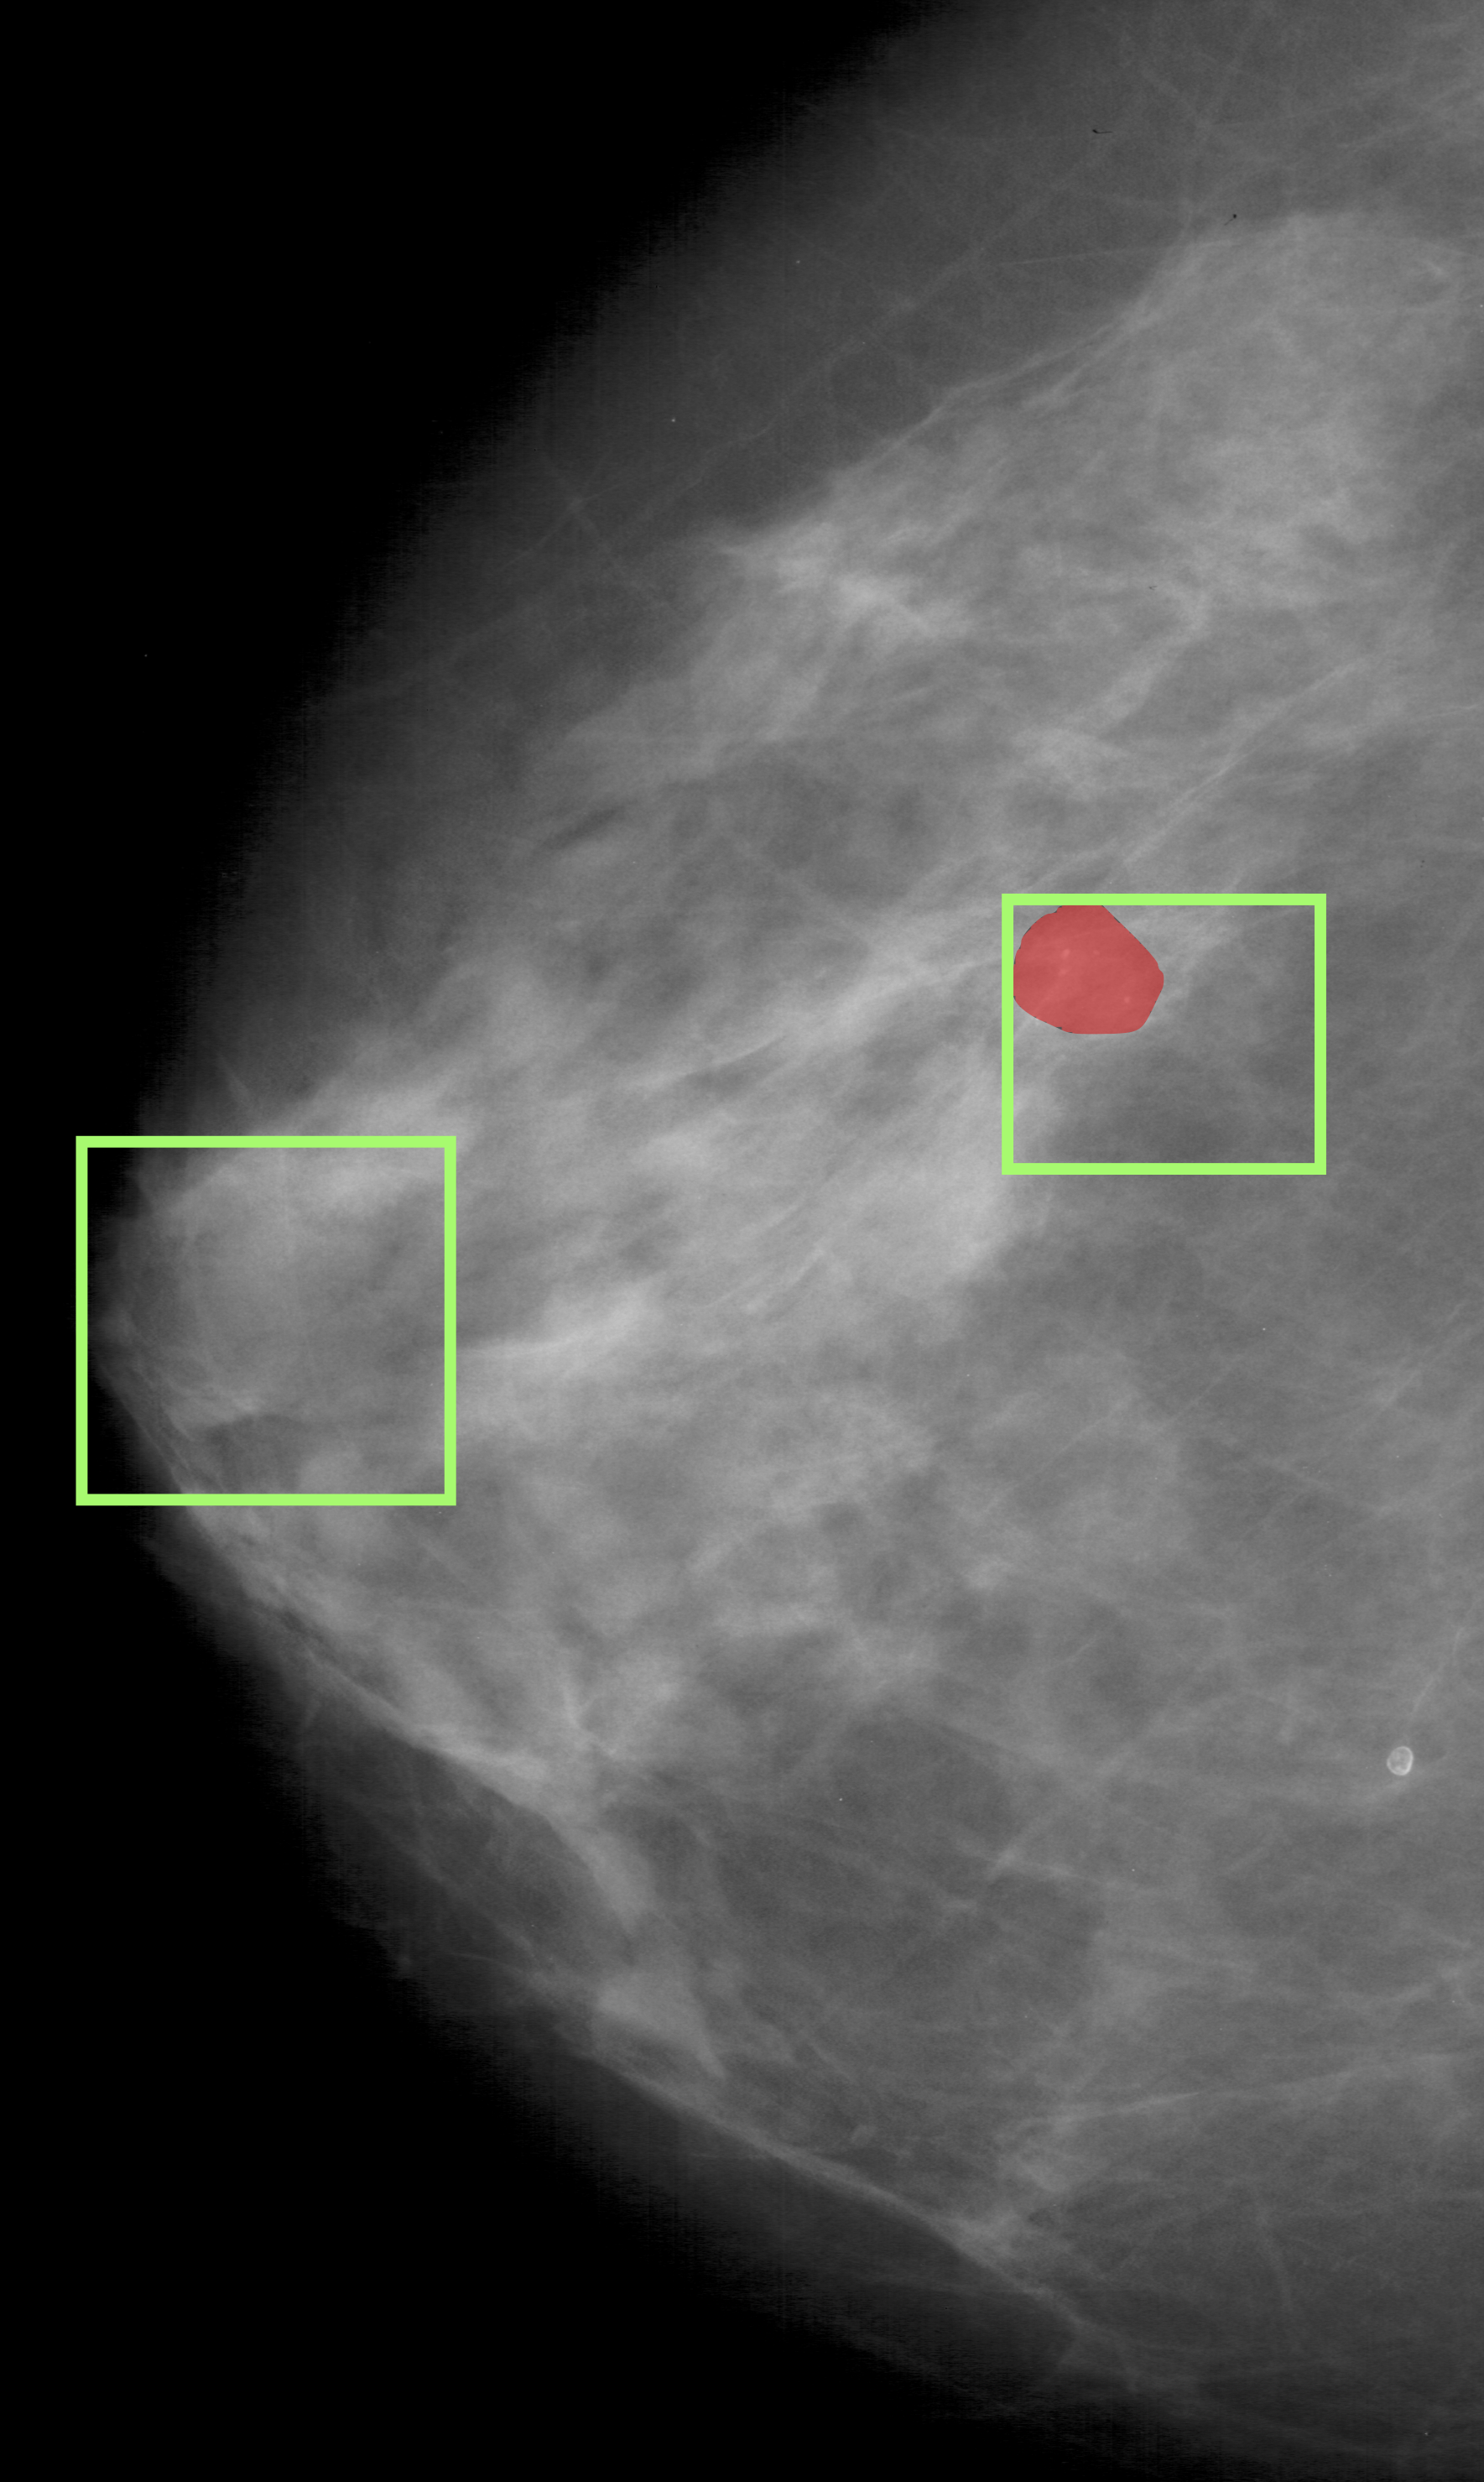

The proposed approach was also applied to breast cancer detection (for screening) from mammograms. Unlike the DME problem, evidence for breast cancer is not easily discernible to the naked, untrained eye and hence is particularly challenging. The 2 classes of interest were defined to be normal and abnormal. The latter includes benign and malignant cases as discrimination between these cases is difficult and best done by a specialised model. The ROI prediction aimed at are suspect regions regardless of whether they are benign or malignant. The architecture used for the DME problem was used and patches from the entire mammogram was fed as input. Training methodology was as described in section 2.3. The patches(200x200) which were classified as positive by the model acts as the predicted ROI in the large sized mammogram image(around 4000x4000 in dimension). The model was assessed on CBIS-DDSM dataset [14]. A total of 5218 training images (2017 abnormal and 3201 Normal) were split into train and validation in the ratio of 12:5. A model trained on 1:3 ratio of annotated images, was evaluated on a test set of 1298 images(709 abnormal and 589 Normal). The AUC/sensitivity(SN)%/specificity(SP)% attained was 0.98/90/93 respectively. Three sample images with ground truth regions and model-predicted ROIs(bounding boxes) are shown in Fig.5. A baseline model(Mbsubscript𝑀𝑏M_{b}) was also trained and tested. It achieved a AUC/SN/SP of 0.972/88.2/ 91.3 respectively. A recent method [15] that does normal/cancerous classification also reports on [14]. It is based on transfer learning with a Resnet50 and reports AUC/SN/SP to be 0.91/86%/80.1%.

Figure 5: Breast cancer detection. Green - Predicted ROI, Red - Ground Truth.